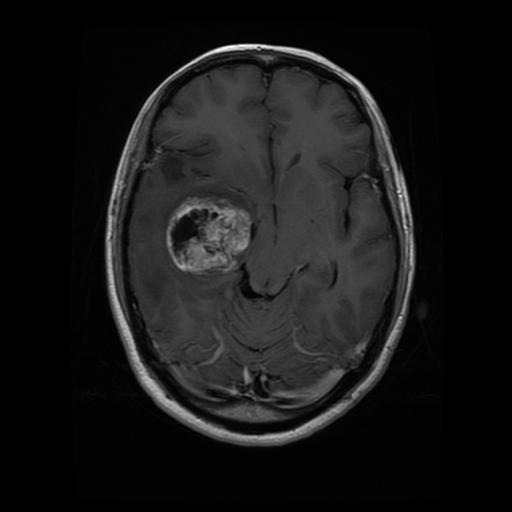

Détection de tumeur grâce à l'IA

Dans ce projet, l'objectif était de développer une méthode de détection de tumeurs en utilisant des techniques de deep learning appliquées aux images médicales. Le processus s'est déroulé en plusieurs étapes clés :

- Prétraitement des données d'images : Traitement initial des images pour améliorer la qualité des données en vue de l'apprentissage, incluant des ajustements de contraste, de netteté, et des opérations de redimensionnement ou de suppression de bruit.

- Utilisation d’autoencodeurs :Développement et utilisation d'autoencodeurs pour effectuer un premier traitement des images et pour extraire des caractéristiques importantes de manière non supervisée, facilitant la segmentation et la reconnaissance des zones potentiellement tumorales.

- Entraînement d’un modèle de deep learning :Mise en place et entraînement d’un modèle de classification (CNN) pour détecter les tumeurs sur les images prétraitées.